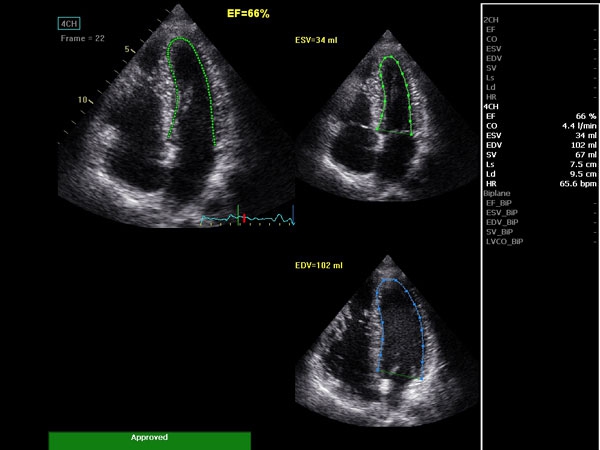

• AutoEF (Auto Ejection Fraction) — функция автоматической недоплеровской количественной оценки глобальной сократительной функции левого желудочка с выделением зоны интереса по технологии спекл-трекинга.

• AFI (Automated Function Imaging) — автоматическое отображение функции ЛЖ — функция позволяет производить качественную и количественную недоплеровскую оценку региональной сократительной функции левого желудочка.

AUTO 2D EF:

Да